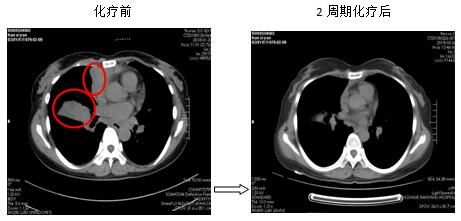

针对每一例化疗患者,参照最新NCCN指南(为肿瘤诊疗的国际权威指南),为患者制定规范、有效的个体化化疗方案。2周期化疗后评价疗效:其中1例肺癌肉瘤术后的胰腺占位的患者,2次化疗后胰腺占位基本消失,另有1例非小细胞肺癌伴肺、心包、肝多发转移患者,2次化疗后肺部、肝内病灶显著缩小,其余化疗患者还未到疗效评价时机(指南推荐每2周期评价化疗疗效)。

图2. 肺癌伴多发转移患者,化疗后肺、心包、肝脏病灶明显缩小